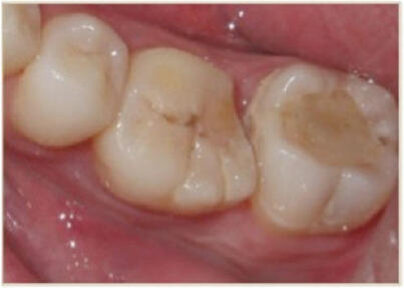

23-letni mężczyzna zgłosił się z bezobjawową zmianą próchniczą w zębie 36, która klinicznie i radiologicznie została rozpoznana jako martwica miazgi z rozległym AP (Ryc. 1). W wywiadzie pacjent nieobciążony. Jako preferowaną metodę leczenia wybrano przeszczep autogenny.

Dane uzyskane metodami radiograficznymi pozwalają na jedynie umiarkowane rozpoznanie, pozwalające odróżnić AP od torbieli korzeniowej.37,38 W opisanym przypadku stan kliniczny zęba 36 uzasadniał ekstrakcję wraz z usunięciem zawartości zmiany (Ryc. 1). Uwzględniając fakt, że przeszczep zęba uznaje się za przewidywalną opcję leczenia, tzw. ząb mądrości często jest najlepszą opcją dawcy.2,39 Niniejszy opis przypadku może stanowić potwierdzenie tej tezy, wraz z uzasadnieniem zabiegu chirurgicznego przeprowadzanego podczas jednej wizyty39,40 oraz istotności leczenia endodotycznego dla pozytywnego rokowania.6,41